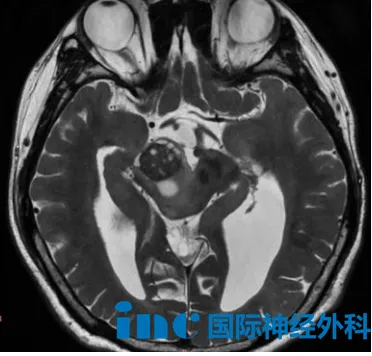

9个月男宝小星星出生3天因脑积水接受脑室-腹腔分流术,8个月大时出现双侧眼睑下垂和斜视,检查发现中脑、四叠体、丘脑区域异常信号,临床怀疑胶质瘤,多数医生建议观察。巴教授强调这可能为中脑弥漫性胶质瘤,单靠手术无法根治,但谨慎选择手术可缩小肿瘤体积,并获得组织病理学与分子生物学诊断结果,为辅助治疗方案提供依据。婴幼儿盲目化疗或放疗风险极高。